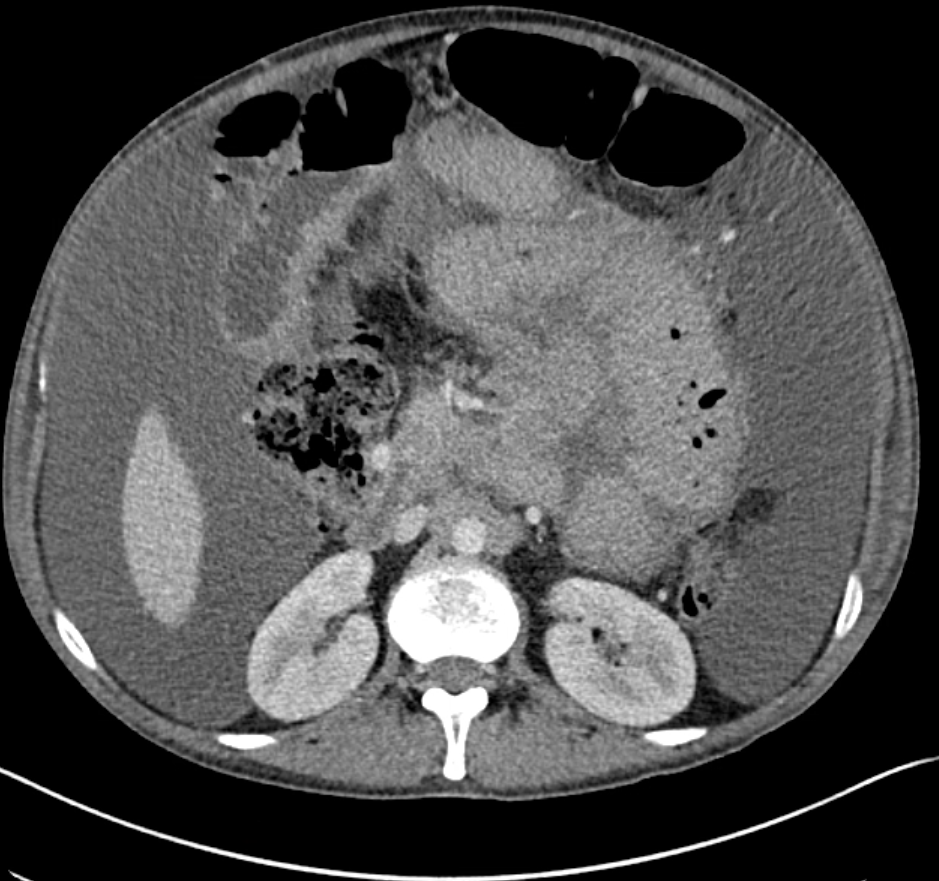

Case Presentation: A 29-year-old male with a history of HIV/AIDs on antiretroviral therapy (ART), prior cryptococcal meningitis, and mycobacterium avium complex (MAC) colitis presented to the ED with a three-week history of worsening abdominal pain and distension. His MAC colitis was diagnosed earlier that year and treated with clarithromycin and ethambutol. However, the ethambutol was discontinued due to concern for optic neuritis, so he was switched to macrolide monotherapy for three months. He had normal vital signs and physical exam showed abdominal distension with a positive fluid shift and diffuse tenderness to palpation without guarding or rebound tenderness. Labs were notable for mild elevation of alkaline phosphatase (192 U/L), anemia (Hgb 10.6 g/dl) and thrombocytosis (607 10³/µL). CT abdomen demonstrated abnormal soft tissue/nodularity along the root of the small bowel mesentery and retroperitoneal lymphadenopathy with ascites and mesenteric edema. He underwent paracentesis which revealed chylous ascites and cultures were positive for MAC. The patient endorsed mild relief of his abdominal symptoms after the paracentesis, but his abdomen became noticeably distended in the days following. After negative ophthalmologic workup, ethambutol was resumed along with azithromycin and rifabutin. He required repeat outpatient paracentesis due to fluid re-accumulation.

Conclusions: Hospitalists should consider MAC colitis with chylous ascites in patients with HIV/AIDs on ART with low CD4 count. Patients may present with nonspecific symptoms and lab abnormalities of anemia, elevated alkaline phosphatase and lactate dehydrogenase. CT is useful to evaluate for lymphatic obstruction secondary to MAC infection. Patients with MAC infections should be treated promptly with a macrolide plus ethambutol. Should ethambutol be discontinued for ophthalmologic concerns, prompt replacement with an appropriate alternative is indicated.